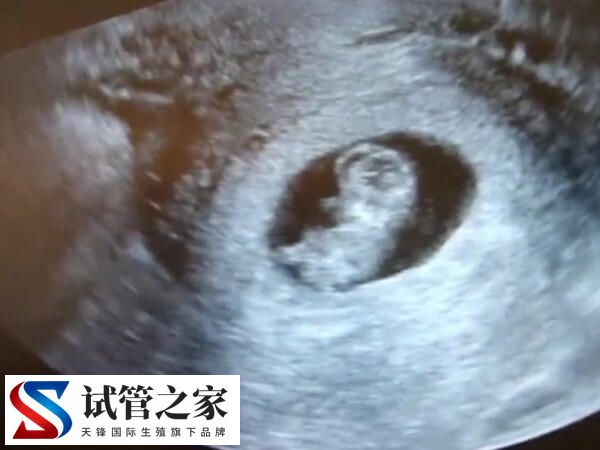

胚胎移植成功并不代表试管婴儿治疗周期的结束,需要通过B超检查来确诊胚胎的着床后的发育情况。试管婴儿在孕早期,是需要进行保胎治疗的。只有顺利通过一超、二超和NT检查,才能正式从生殖中心毕业。这些检查都非常重要,它能观察孕囊在宫腔的位置、监测胎儿的生长发育情况以及胎儿严重结构畸形筛查,从而降低缺陷儿的出生率。

在试管婴儿移植后,为监测孕囊的部位、胎儿的生长发育情况,降低畸形儿和有缺陷儿的出生率,早孕期阴道B超检查显然是很必要的。而且也不用担心B超检查会对胚胎发育造成影响,是因为B超检查产生的影响很小。

- 2、核实孕周、判断胚胎发育情况。根据孕囊的平均直径、胎芽大小、胎儿的头臀长判断孕龄,有助于中晚孕期间判断胎儿发育的状况。经阴道B超胎芽大于5mm时,应该见到胎心搏动。如果没有见到胎心搏动,提示有胚胎停止发育 的可能,应定期复查。